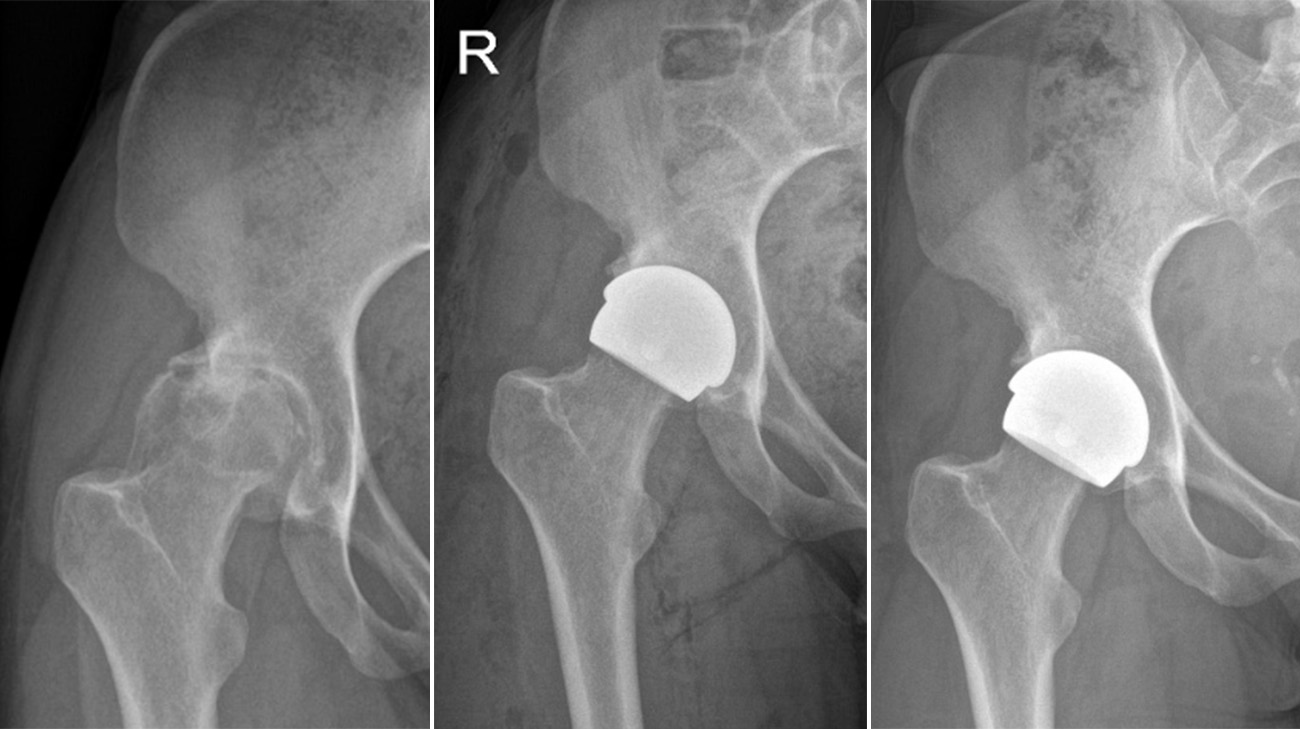

Georgina's hip joint before and after surgery with the ceramic hip resurfacing in place. The X-rays show the pelvis and spine returning to alignment. (Courtesy: Cleveland Clinic)

Instead of replacing the entire hip joint, a resurfacing surgery involves replacing only the hip socket with a prosthetic piece. The ceramic implant Georgina received is tailored specifically for patients with smaller hips and pelvises. (Courtesy: Cleveland Clinic)

Georgina came to Prof Cobb at the right time. For years, the only available option was metal-on-metal hip resurfacing, which manufacturers currently recommend only for patients with larger femoral heads – typically found more often in men. This design is less suitable for individuals with smaller bone structures, including many women and others with narrower hips, who are more likely to experience pain and require early revision after the procedure. In response to this limitation, Prof Cobb and a team of developers created an innovative ceramic hip resurfacing implant called the H1, tailored specifically for patients with smaller hips and pelvises.

“The ceramic implant is designed to address the limitations of metal-on-metal implants, expanding hip resurfacing access to patients who previously wouldn’t have been candidates for it,” says Prof Cobb, adding a 2023 clinical study found women who received the ceramic implant had postoperative biomechanics similar to healthy women who didn’t have hip surgery.